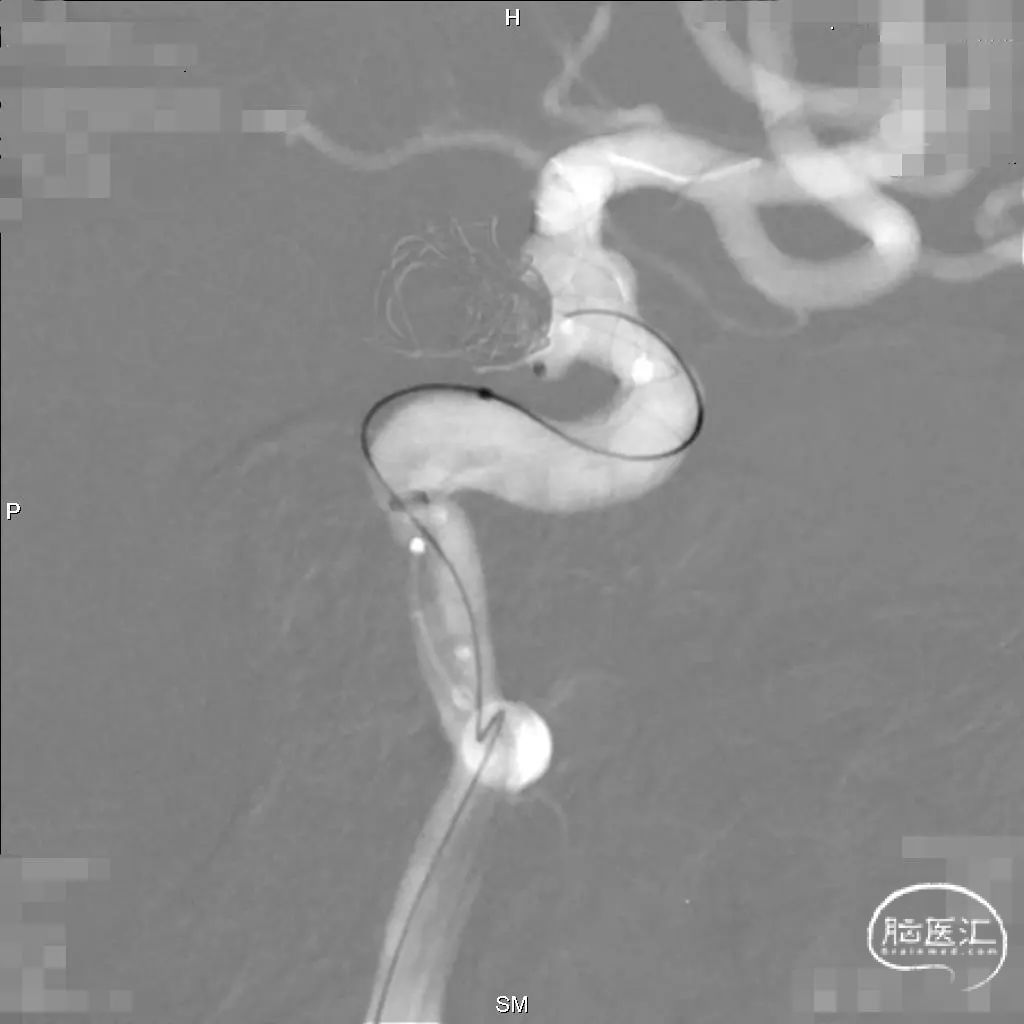

密网支架释放

支架释放前后对比

填塞动脉瘤